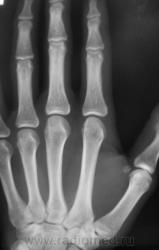

Травма. Пациент направлен на рентгенографию 2 пальца.

Костно-травматических изменений не вижу

Вот это прикол. Настоящая головоломка !!! это инородное тело в области мед края головки осн фаланги 2 пальца.

Ну, не знаю. я тоже ничего не вижу. А тонюсенькая полосочка может быть и артефактом.

По всей видимости, норму надо писать?

Валентин Львович, вы ж укажите, где локальная болезненность. Может перелом основания осн. фаланги?

??? Головка ср.ф. какая-то скошенная, но деструктивн. изм., повреждений не вижу.

Меня тоже смутила форма головки фаланги.